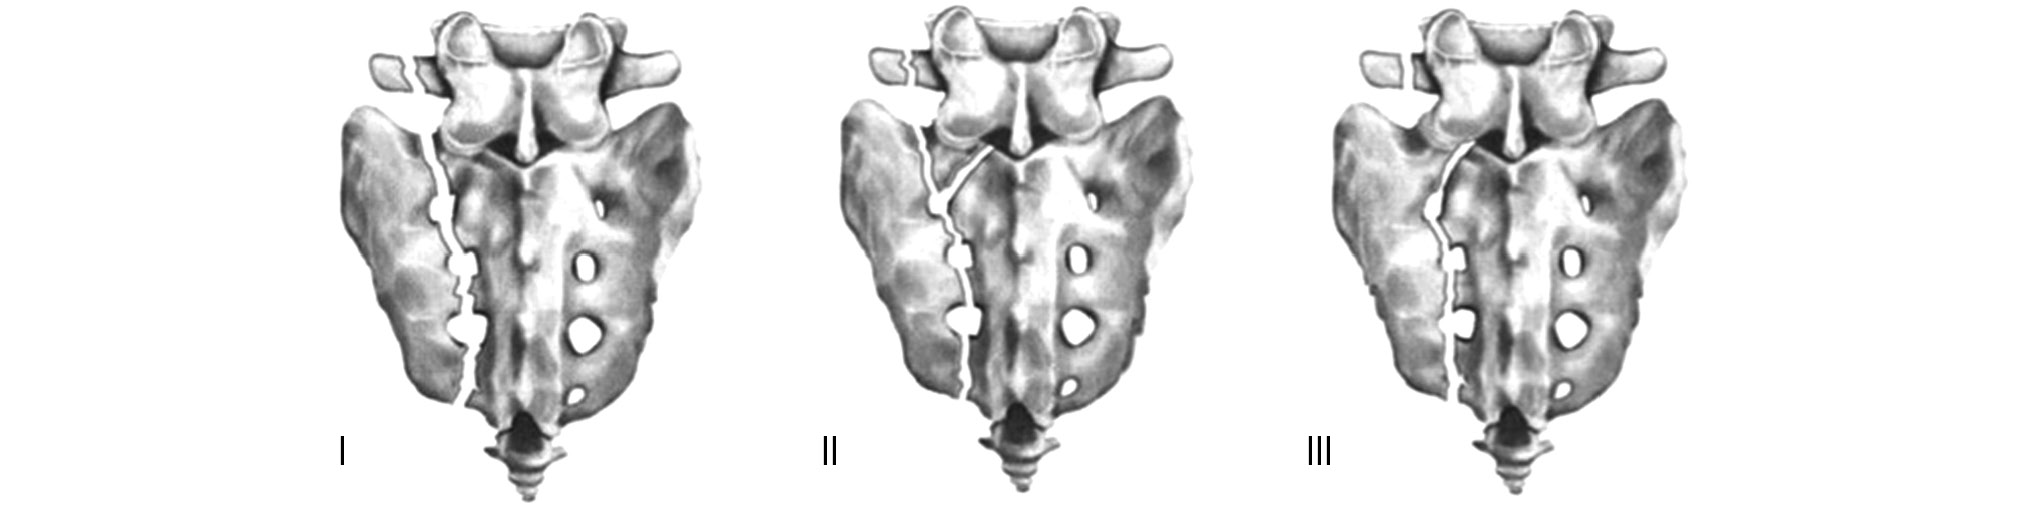

Классификации повреждений крестца делятся в зависимости от варианта прохождения линии перелома относительно крестцовой кости (продольные, поперечные или комбинированные в виде H-, U-, λ- или Т-образных форм; рис. 3). Продольные переломы являются наиболее распространёнными (90%) [5], поперечные составляют всего 3–5% всех переломов крестца (они же ещё подразделяются на высокие или низкие) [8], а на комбинированные переломы, такие как U-, H-, Т- или λ-образные, приходится 3–6% всех случаев переломов крестца [9].

Рис. 3. Классификация комбинированных переломов крестца по прохождению линии перелома крестца: I — U-образный; II — H-образный; III — Т-образный; IV — λ-образный [9].